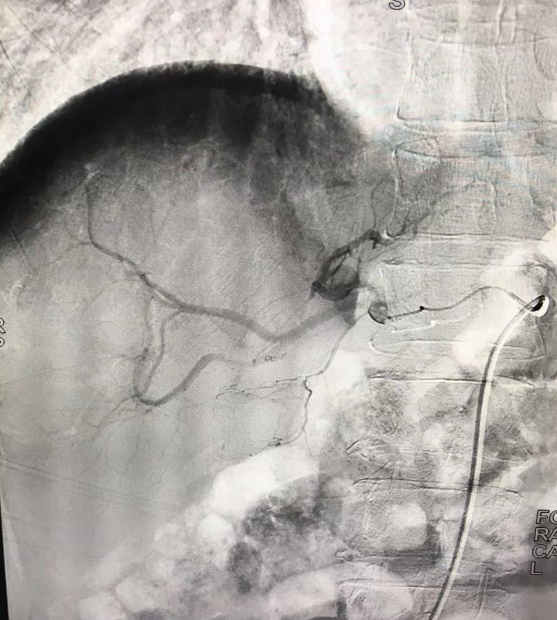

術(shù)前造影顯示腫瘤由肝動脈分支供血,血管增粗屈曲,腫瘤染色顯影明顯。

術(shù)后造影顯示血管栓塞良好,腫瘤未見明顯染色。